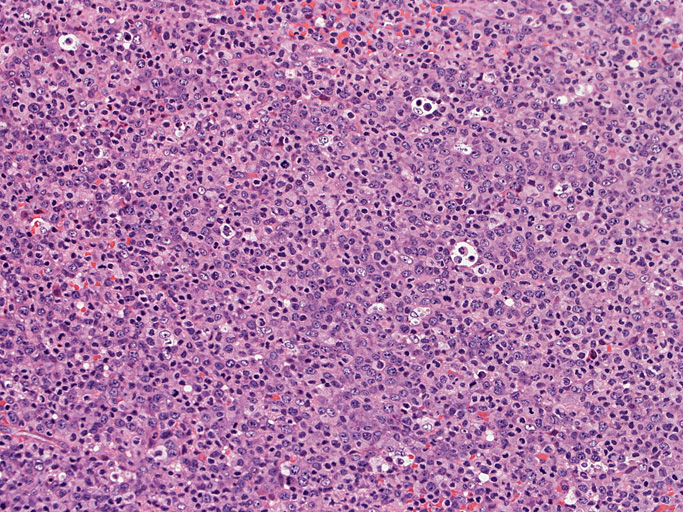

頸部リンパ節病理組織所見

いわゆるanaplastic large cellと呼ぶ多型または腎臓型核をもった大型細胞の増殖はみられない。centroblastに似る円形, 卵円形, わずかに切れ込みをもつ核をもつ大型細胞が索状または地図様に集ぞくし, 背景には淡明な細胞質としわのよったhypercrhomaticな核をもつ細胞がシート状に認められる。二種類の細胞がHEでは認められる。

ALK-positive ALCLのvariant, lymphohistiocytic variantが近いと考える